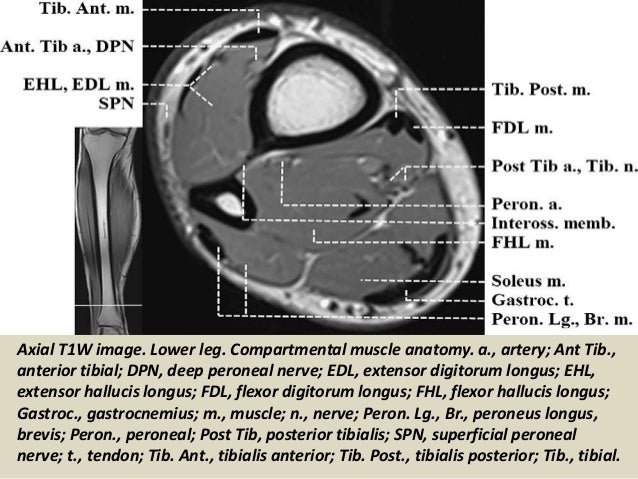

Whether it's to pass that big test, qualify for that big promotion or even master that cooking technique; The adductor muscles form the fleshy mass on the medial side of the thigh. Both the thigh and leg are divided into three separate compartments. Anterior superior iliac spine insertion: Human anatomy » musculoskeletal system » the muscles of the arm and hand. Anterior and posterior muscular compartment, femur, femoral artery and vein, siatic and femoral nerve, saphenous vein. Magnetic resonance imaging (mri) can be beneficial in identifying adductor brevis or adductor longus muscle atrophy which would indicate possible obturator nerve entrapment. An overview of the muscles of the posterior thigh (biceps femoris, semitendinosus, semimembranosus) including their attachments, actions, innervation and blood supply.

Human anatomy » musculoskeletal system » the muscles of the arm and hand. Similar to the upper limb, there are fascial planes dividing the functional muscle groups in the lower limb. The thigh has some of the body's largest muscles. The uppermost of the medial thigh muscles is the pectineus muscle. The gold standard for diagnosis of this condition is electromyography. Learn about thigh muscle anatomy with free interactive flashcards. Both the thigh and leg are divided into three separate compartments. Using mri as the reference method, muscle volume was predictedfrom anthropometry using a circular. As the name implies they adduct the thigh at the hip. Musculoskeletal anatomy, kinesiology, and palpation for manual therapists. The anterior femoral muscles (fig. Upper medial surface of the shaft of the tibia in front of the insertions of the gracilis and the semitendinosus nerve supply: The thigh is the area between the hip and the knee joint.

The muscles and fasciæ of the thigh. Using mri as the reference method, muscle volume was predictedfrom anthropometry using a circular. Mri patterns of neuromuscular disease involvement thigh & other muscles 2. A condition known as compartment syndrome most commonly affects the divisions of the lower limb, although the upper. Muscle mri can provide information that is complementary to clinical, histologic, genetic, and laboratory findings for the diagnosis of neuromuscular disease. The deltoid muscle is a rounded, triangular muscle located on the uppermost part of the arm and the top of the shoulder. Dummies helps everyone be more knowledgeable and confident in applying what they know. While the thigh muscles will be slip into the anterior, medial and posterior groups. We think this is the most useful anatomy picture that you need. There are around 650 skeletal muscles within the typical human body. Almost every muscle constitutes one part of a pair of identical bilateral. You can click the image to magnify if you cannot see clearly. Typical findings are edema, hematoma, and partial or complete muscles tears.